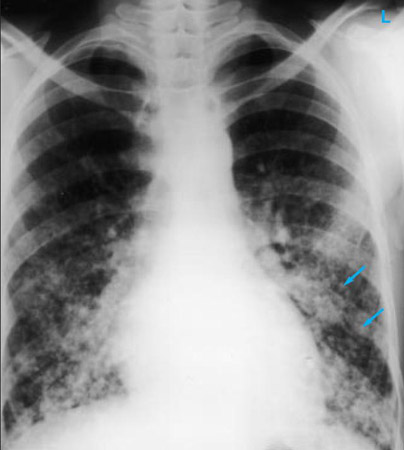

Uma radiografia torácica deve ser obtida no início da avaliação da tosse crônica.[38] Embora não seja diagnóstica das causas mais comuns, os achados podem facilmente desviar a avaliação para causas de maior gravidade como doenças pulmonares estruturais. Eles incluem câncer pulmonar, fibrose pulmonar, tuberculose, bronquiectasia, pneumonia, aspiração e sarcoidose.[Figure caption and citation for the preceding image starts]: Radiografia torácica mostrando hiperinsuflação em paciente com DPOC. A hiperinsuflação é causada pelo componente de enfisema na DPOC, em vez da bronquite crônica subjacente aos sintomas da tosseDo acervo pessoal do Dr. M. A. Sharifabadand, SUNY na Stony Brook School of Medicine, Departamento de Medicina Pulmonar e Intensiva, Mineola, Nova York, e Dr. J. P. Parsons, The Ohio State University Medical Center, Columbus; usado com permissão [Citation ends].

[Figure caption and citation for the preceding image starts]: Radiografia torácica mostrando adenopatia hilar bilateral em um paciente com sarcoidoseDo acervo pessoal do Dr. M.P. Muthiah, Divisão de Medicina Pulmonar e Intensiva e Medicina do Sono, Universidade do Tennessee [Citation ends].